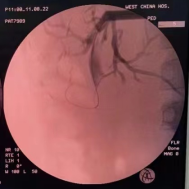

考虑患儿肝移植手术腹腔粘连紧密及局部解剖位置改变,开腹手术难度较大。多学科团队多次进行会诊讨论,最后决定先行经皮肝穿刺胆道引流(PTCD)减轻炎症及黄疸,术中同时取肝脏活检进一步明确诊断。患儿术后胆汁引流通畅,肝功恢复正常。待原吻合口炎症水肿消退及经皮穿刺隧道稳定后,患儿于6月1日在全麻下行胆道镜取石,取石完成后术中胆道造影可见造影剂通过胆肠吻合口,继续放置T管引流,1个月后经T管造影提示肝内外胆管通畅,造影剂可进入肠腔。随后,患儿于8月11日在全麻下行经皮胆道镜检查,经原PTCD皮肤窦道置入胆管镜,在胆道镜直视下导丝引导置入4mm球囊扩张器反复扩张原胆肠吻合口(图2-4),扩张完成后胆道镜可轻松通过胆肠吻合口进入空肠,造影显示吻合口通畅(图5),放置适当直径引流管支撑引流,术后患儿无特殊不适。

图1:移植肝肝内胆管可正常显影,胆肠吻合口明显狭窄,造影剂不能通过胆肠吻合口进入空场